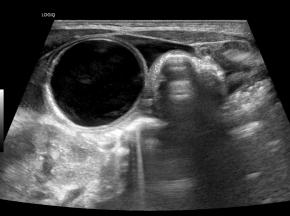

[359,Pediatric [Ped]] 1/F,Abdominal cyst was detected on prenatal ultrasound.

Modality US,

실제 이미지 실제 이미지